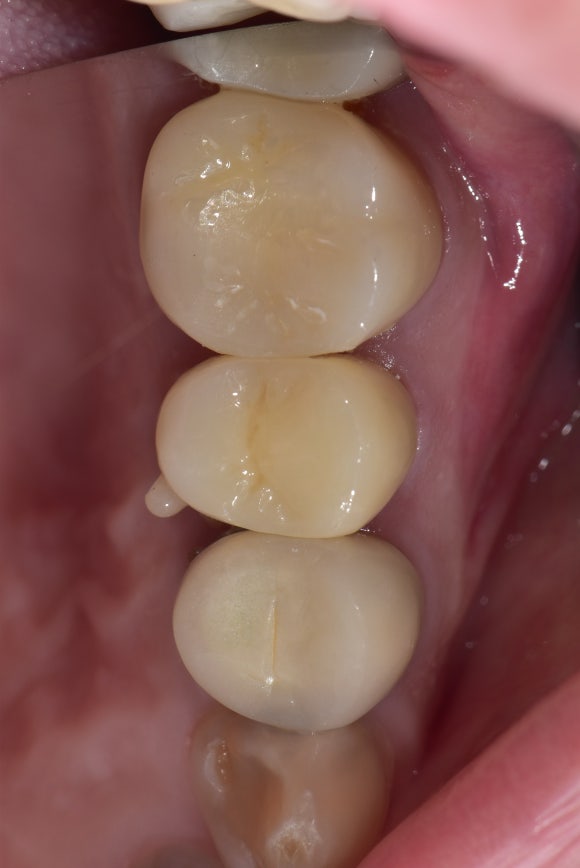

20240411

치료 전 사진입니다.

이전에 신경치료한 것이 약간 허술해보입니다.

옛날에는 영상 기술이나 기구, 재료가 지금만큼 우수하지 못했기 때문입니다.

그러나 구강 내에서 수년을 불편감없이 버텨냈습니다. 십년을 넘게 쓰시는 경우도 심심치않게 보입니다.

엑스레이상으로 어떻게 보이느냐보다는

실제로 환자분의 불편감과 이어지느냐가

재신경치료를 할지 말지를 결정한다고 보시면 되겠습니다.